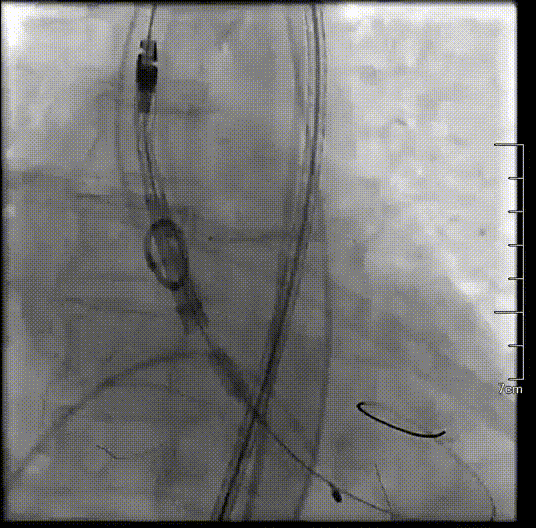

瓣膜释放到可回收临界点

临界点处造影